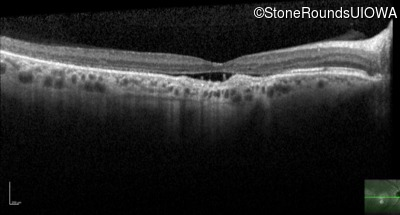

Optical Coherence Tomography - Left - 20/100

Exemplar / OCT Stack

OCT Stack